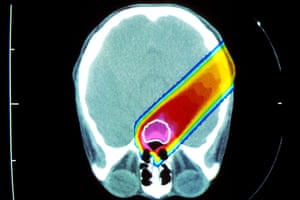

Many anti-cancer therapies are known to destroy fertility either chemically or through radiation, but many other factors will affect whether or not cancer survivors go on to have children. “As well as the treatment damaging their fertility, it’s also women choosing not to complete their family,” said Anderson. “Some women may not want to bring another child into the world when they are not sure about their own health.”

The work highlights the need for more widespread access to new procedures that aim to preserve the fertility of girls and women who face cancer therapy. One approach is to remove ovarian tissue from the patient and freeze it until the patient has the all-clear and the tissue can be re-implanted. Last year, Anderson announced the first British birth using frozen ovarian tissue, to a 33-year-old woman who had part of an ovary removed 11 years earlier. Anderson said the latest findings should help doctors to counsel women who are diagnosed with cancer and direct services, such as ovarian tissue preservation, to where it is needed most.